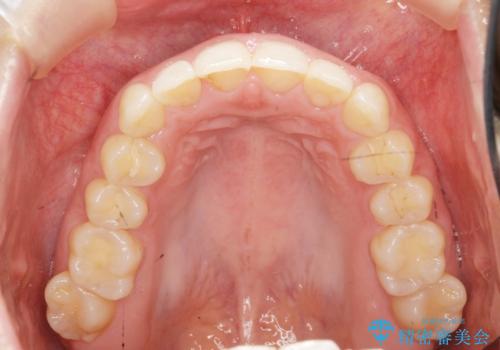

出っ歯に見える前歯の改善 部分ワイヤーとマウスピース矯正

- 出っ歯に見える前歯の改善を希望され、来院されました。

マウスピースでは改善の難しい歯の動きを部分ワイヤー矯正で整えたのち、奥歯の噛み合わせや細かい歯の並びをマウスピース矯正インビザラインで整えていきます。

最終的な前歯の並びに大変満足いただくことができました。